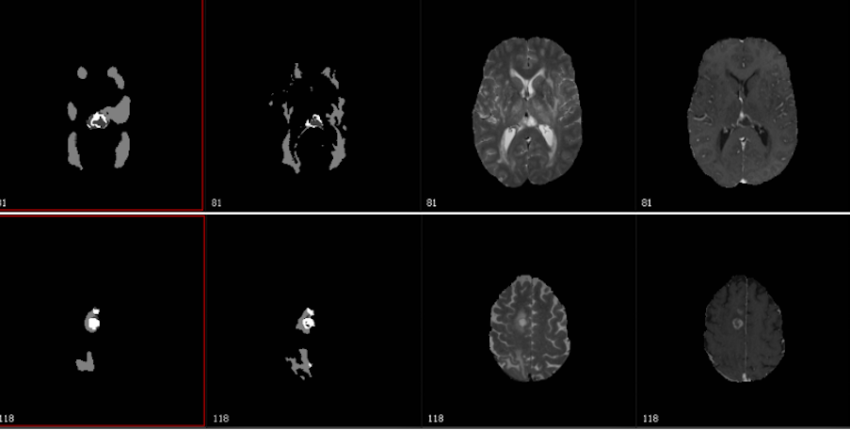

Supercomputer herkent hersentumoren